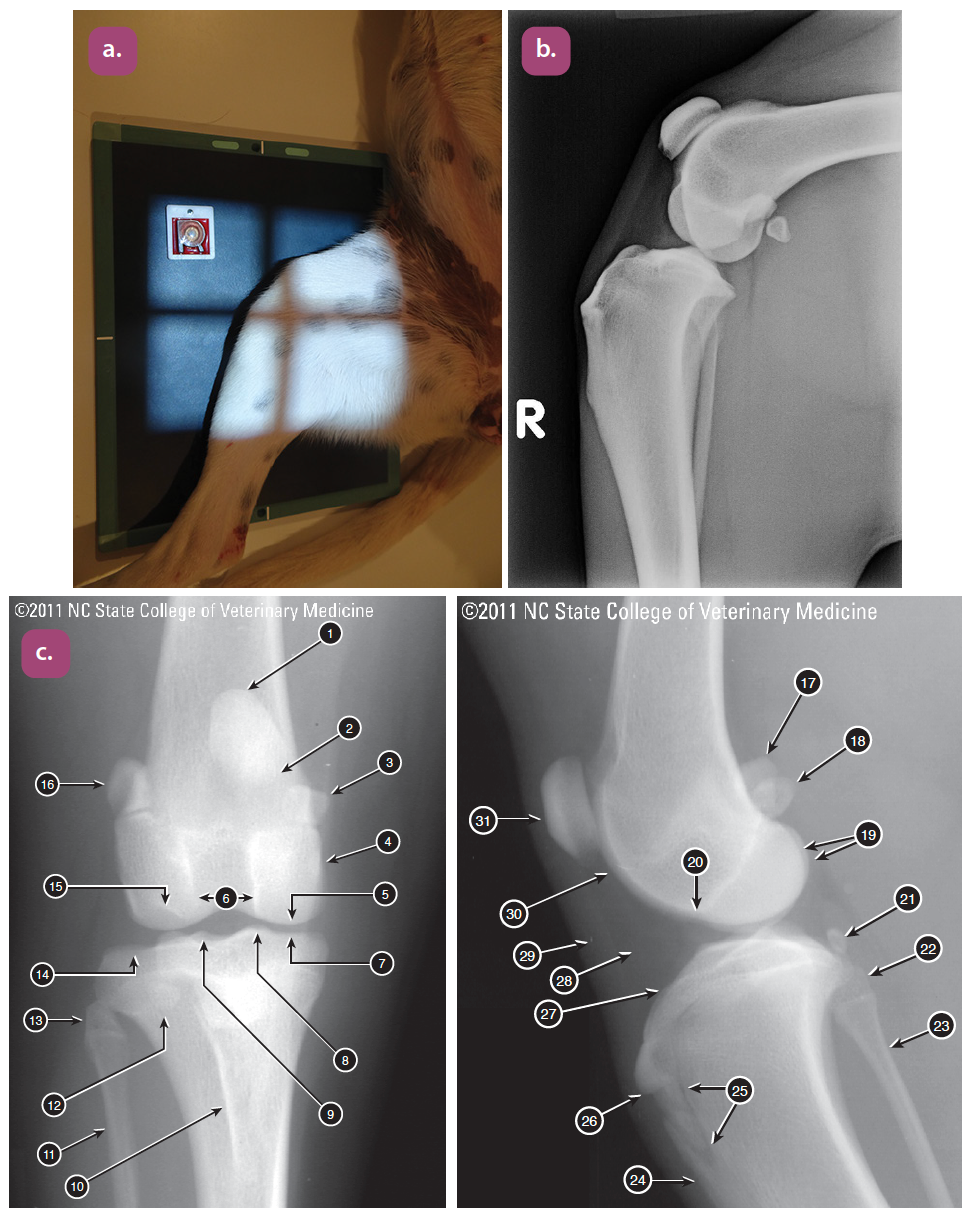

mediolateral projection of the stifle

Caudocranial projection of the stifle